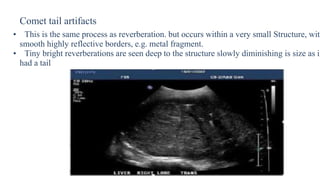

Comet tail artifacts

• This is the same process as reverberation. but occurs within a very small Structure, with

• Tiny bright reverberations are seen deep to the structure slowly diminishing is size as if

had a tail